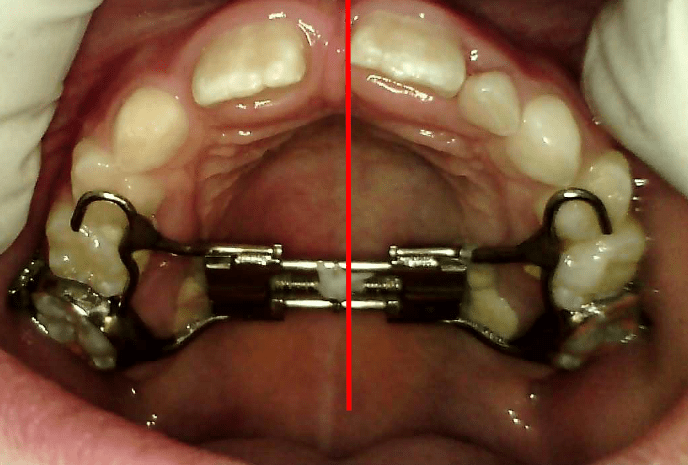

RAPID MAXILLARY EXPANSION

USED ON CASES WHERE THE DENTAL ARCH IS TOO SMALL TO ACCOMODATE THE UNERUPTED DENTITION Rapid Maxillary Expansion (RME) Appliance: What It Is and How It Works This appliance is commonly used in children and teenagers to widen the upper jaw (maxilla) when it is too narrow. A narrow jaw can cause problems like crowding… Read.